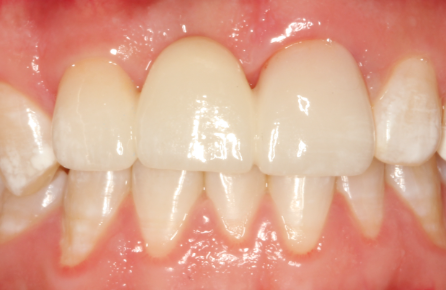

二、固定义齿(固定桥):折中的“桥梁方案”

什么是固定桥?

顾名思义,它就像在缺牙区架起一座“桥”。“桥墩”是缺失牙两侧经过打磨的健康牙齿(称为基牙),“桥体”就是修复的假牙。整个修复体通过粘接剂牢固地固定在基牙上,患者无法自行取下。

图2.固定桥修复

它的核心特点:

优点:

1.  舒适美观: 没有基托,异物感小,外形和颜色都更接近天然牙,美观度高。

2.  咀嚼功能好: 稳定性强,咀嚼效率近似天然牙,使用体验接近真牙。

3.  使用方便: 无需每日摘戴,日常护理如同正常刷牙,非常便利。

缺点:

1.  不可逆的损伤: 这是最大的代价。为了给“桥墩”戴上传送力量的牙冠,需要将两侧健康的基牙磨小一圈。这是一种永久性的、不可逆的损伤。

2.  适应证严格: 对“桥墩”的要求极高,要求邻牙必须足够坚固、健康。如果基牙本身就有问题,此方案便不适用。

3.  清洁挑战: “桥体”下部与牙龈之间存在微小间隙,容易塞牙且难以清洁,需要借助牙线穿引器等特殊工具,否则易导致基牙蛀坏或牙周炎。

4.  “一损俱损”的风险: 一旦任何一个“桥墩”出现问题,整个固定桥都需要拆除重做。

最适合人群: 邻牙本身就有较大缺损(如已做过根管治疗需做牙冠保护)、缺牙间隙不大、且患者非常追求舒适与美观,同时不愿或不能接受种植牙的情况。在种植技术日益成熟的今天,固定桥的应用已逐渐减少。